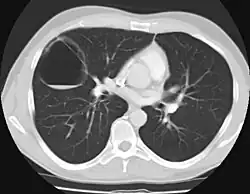

Congenital pulmonary airway malformation (CPAM), formerly known as congenital cystic adenomatoid malformation (CCAM), is a congenital disorder of the lung similar to bronchopulmonary sequestration. In CPAM, usually an entire lobe of lung is replaced by a non-working cystic piece of abnormal lung tissue. This abnormal tissue will never function as normal lung tissue. The underlying cause for CPAM is unknown. It occurs in approximately 1 in every 30,000 pregnancies.[1]

In most cases the outcome of a fetus with CPAM is very good. In rare cases, the cystic mass grows so large as to limit the growth of the surrounding lung and cause pressure against the heart. In these situations, the CPAM can be life-threatening for the fetus. CPAM can be separated into five types, based on clinical and pathologic features.[2] CPAM type 1 is the most common, with large cysts and a good prognosis. CPAM type 2 (with medium-sized cysts) often has a poor prognosis, owing to its frequent association with other significant anomalies. Other types are rare.[3]

CPAMs are classified into three different types based largely on their gross appearance. Type I has a large (>2 cm) multiloculated cysts. Type II has smaller uniform cysts. Type III is not grossly cystic, referred to as the "adenomatoid" type. Microscopically, the lesions are not true cysts, but communicate with the surrounding parenchyma. Some lesions have an abnormal connection to a blood vessel from an aorta and are referred to as "hybrid lesions."

The earliest point at which a CPAM can be detected is by prenatal ultrasound. The classic description is of an echogenic lung mass that gradually disappears over subsequent ultrasounds. The disappearance is due to the malformation becoming filled with fluid over the course of the gestation, allowing the ultrasound waves to penetrate it more easily and rendering it invisible on sonographic imaging. When a CPAM is rapidly growing, either solid or with a dominant cyst, they have a higher incidence of developing venous outflow obstruction, cardiac failure and ultimately hydrops fetalis. If hydrops is not present, the fetus has a 95% chance of survival. When hydrops is present, risk of fetal demise is much greater without in utero surgery to correct the pathophysiology. The greatest period of growth is during the end of the second trimester, between 20 and 26 weeks.